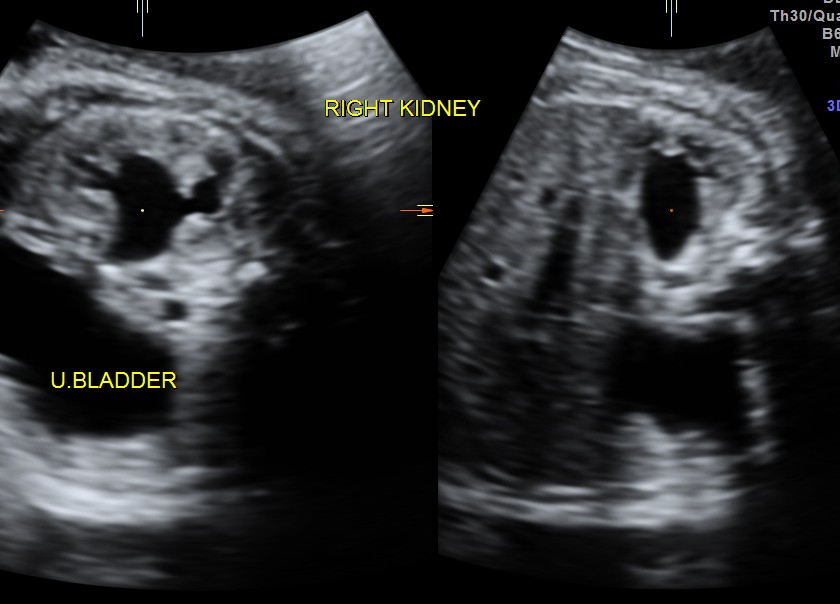

The fetus also showed bilateral pelvi calyectasis and rt ureteromegaly.